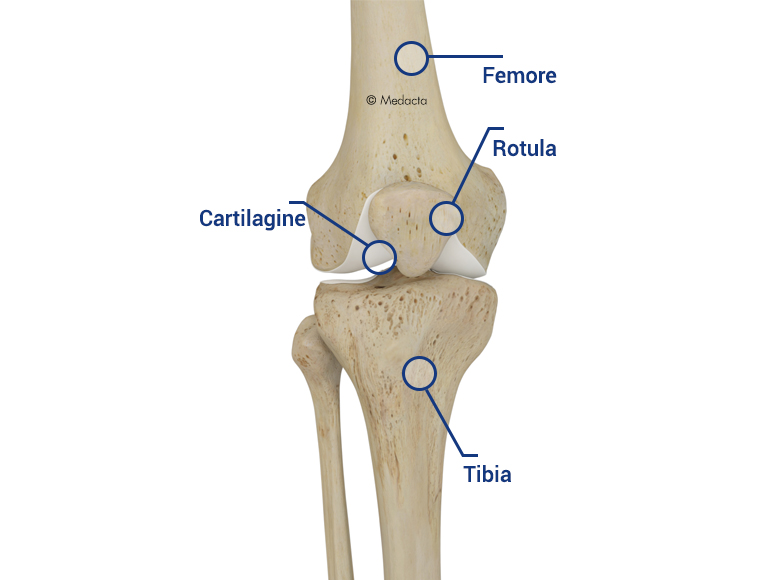

Apex patellae

Apex patellae 117 фото